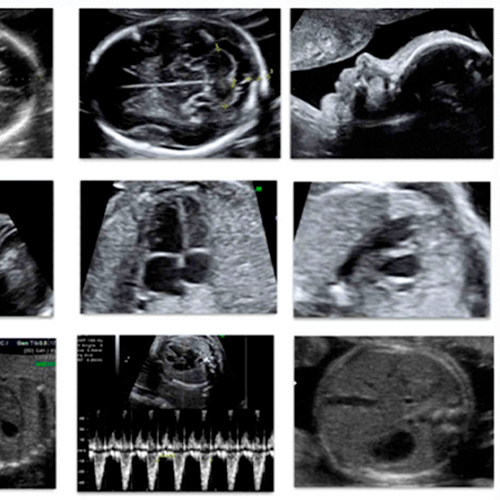

Ecografías